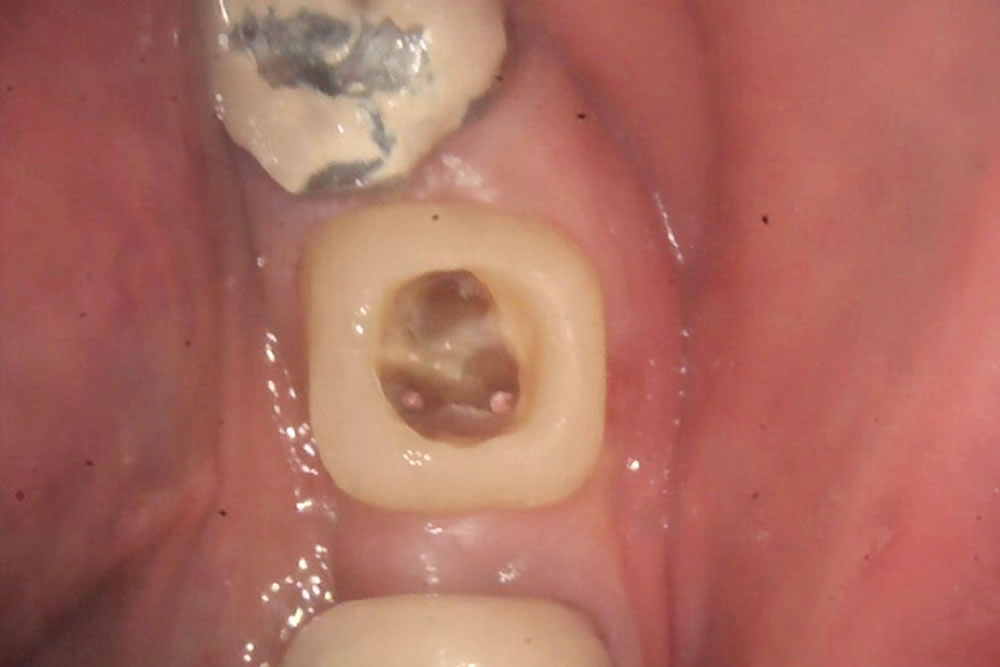

被せ物と土台を外したため、過去に根管治療を行った際のゴム状の材料が見えている状態です。

根管治療を行う際は、治療の成功率を向上させるためにプラスチックの材料で一時的に土台を作り、治療中に唾液が入らないようにします。